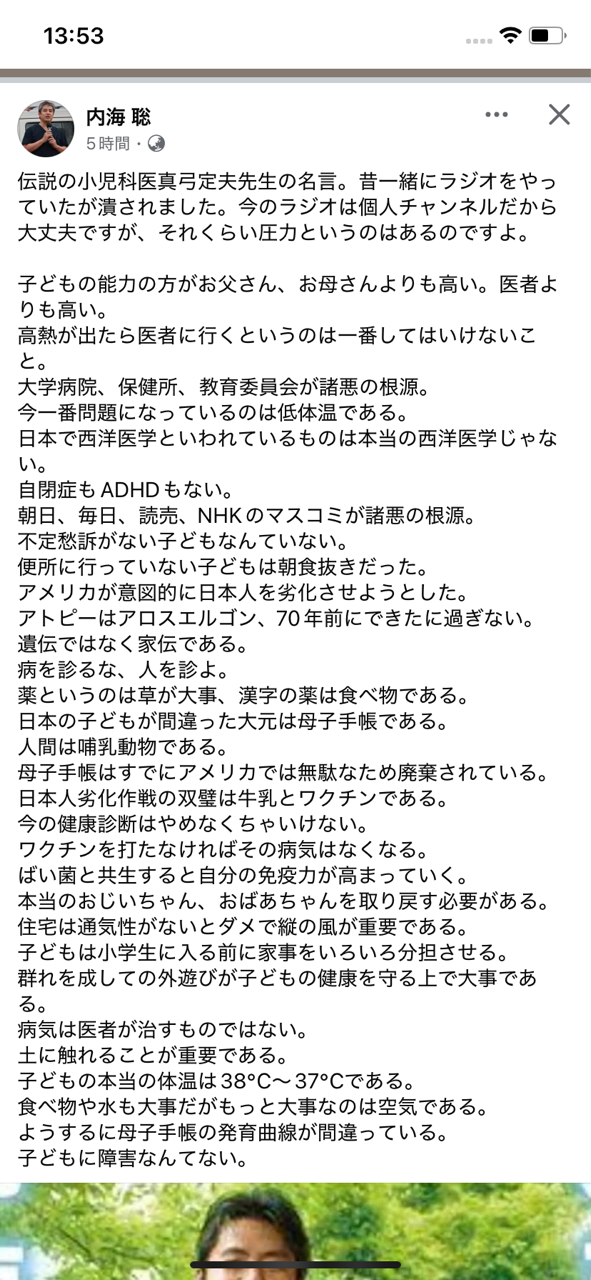

伝説の小児科医真弓貞夫先生の名言 出典・フェイスブック

iPhoneから送信

2025.01.12